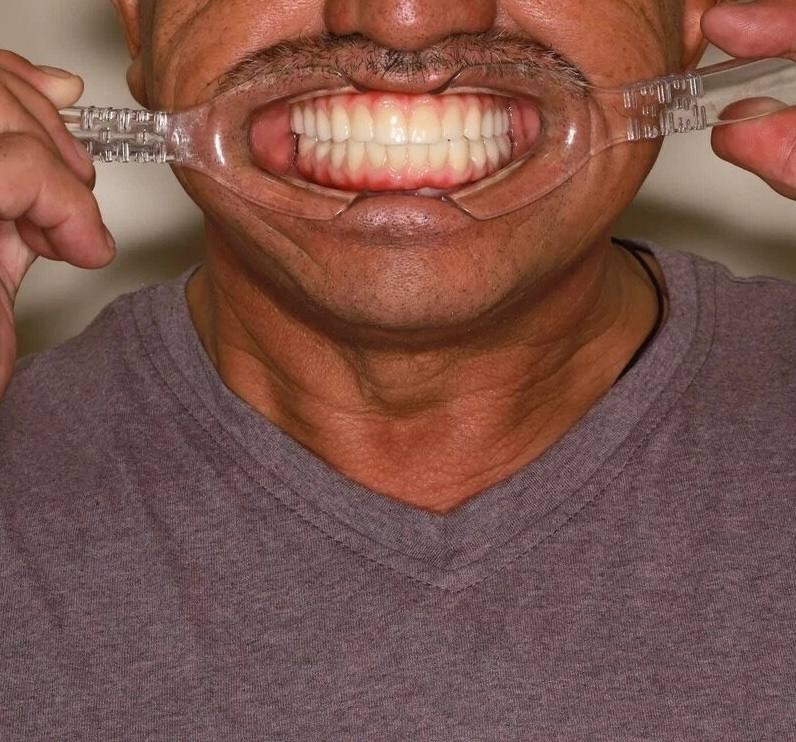

На странице представлено портфолио стоматологий Самары с фото работ до и после имплантации зубов. Мы собрали разные клинические случаи: одиночные импланты, восстановление нескольких зубов и полная реконструкция зубного ряда. Здесь вы можете видеть, как выглядят восстановленные зубы, меняется форма улыбки после процедуры. Изучите результаты до и после имплантации зубов, чтобы оценить качество работы врачей и выбрать стоматологию в Самаре, которая поможет вернуть функциональность и эстетику вашей улыбке.

Имплантация All-on-4

Пациентка, 65 лет обратилась с целью протезирования. На верхней челюсти изготовлен полностью съемный постоянный протез, а на нижней челюсти проведено удаление всех зубов (хронический пародонтит IV степени тяжести) и одномоментно установлено 4 дентальных имплантата «Nobel Biocare» по концепции «Всё-на-4 (All-in-4)» и временные мосты на имплантатах. Спустя 2,5 месяца проведена замена временных зубов на металлокерамический мост из 12 единиц с опорой на 4 имплантата.